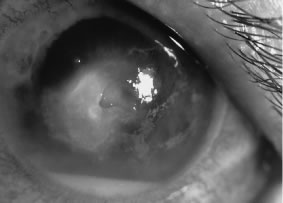

Candida infection typically produces epithelial ulceration, focal necrotizing stromal inflammation, moderate cellular infiltrate and edema in the adjacent stroma, and mild or moderate iritis in the early stages, indistinguishable from bacterial keratitis (Figs. 15, 16, and 17). Fungal elements cannot be detected by biomicroscopy. If untreated, the keratitis evolves to produce dense suppuration and necrosis of the deep stroma. Although multifocal suppuration may develop in polymicrobial keratitis, there is no distinctive sign of mixed Candida and bacterial infection (Fig. 18).

Fig. 17. C. albicans in a 21-year-old woman. Topical proparacaine hydrochloride abuse. Epithelial and stromal ulceration. Note the dense, white area of necrotizing stromal keratitis.